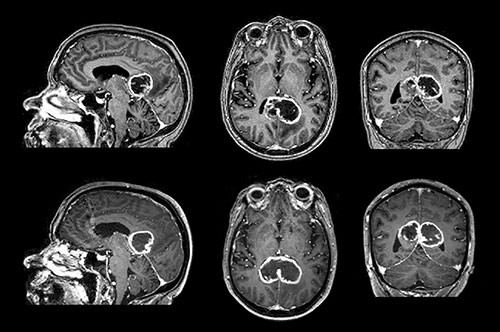

The figure shows contrast-enhanced T₁-weighted MRI images of a butterfly glioma with strong peripheral contrast enhancement and central necrosis, typical of a glioblastoma. Butterfly gliomas most frequently infiltrate the genu of the corpus callosum (≈ 60 %), and less often the body (≈ 30 %), and splenium (≈ 10 %) (1). Symptomatically, such tumours may result in disconnection syndromes such as alexia, agraphia and apraxia, rather than ordinary sensomotoric deficits. For example, unilateral apraxia may occur if the language areas in the left hemisphere are disconnected from the motor areas in the right hemisphere. Instructed verbally to perform tasks, the patient will be unable to perform them with his left hand, but able to perform them with his right hand.

The lower part of the figure shows the same tumour after 16 days, where it has grown from 27.4 cm³ to 37.6 cm³, a 37 % increase in volume. This translates into a doubling time of 32 days, assuming exponential growth. There are few systematic in vivo studies in the literature of glioblastoma growth rates and doubling times. The few existing studies estimate doubling times at from 10 to 95 days.